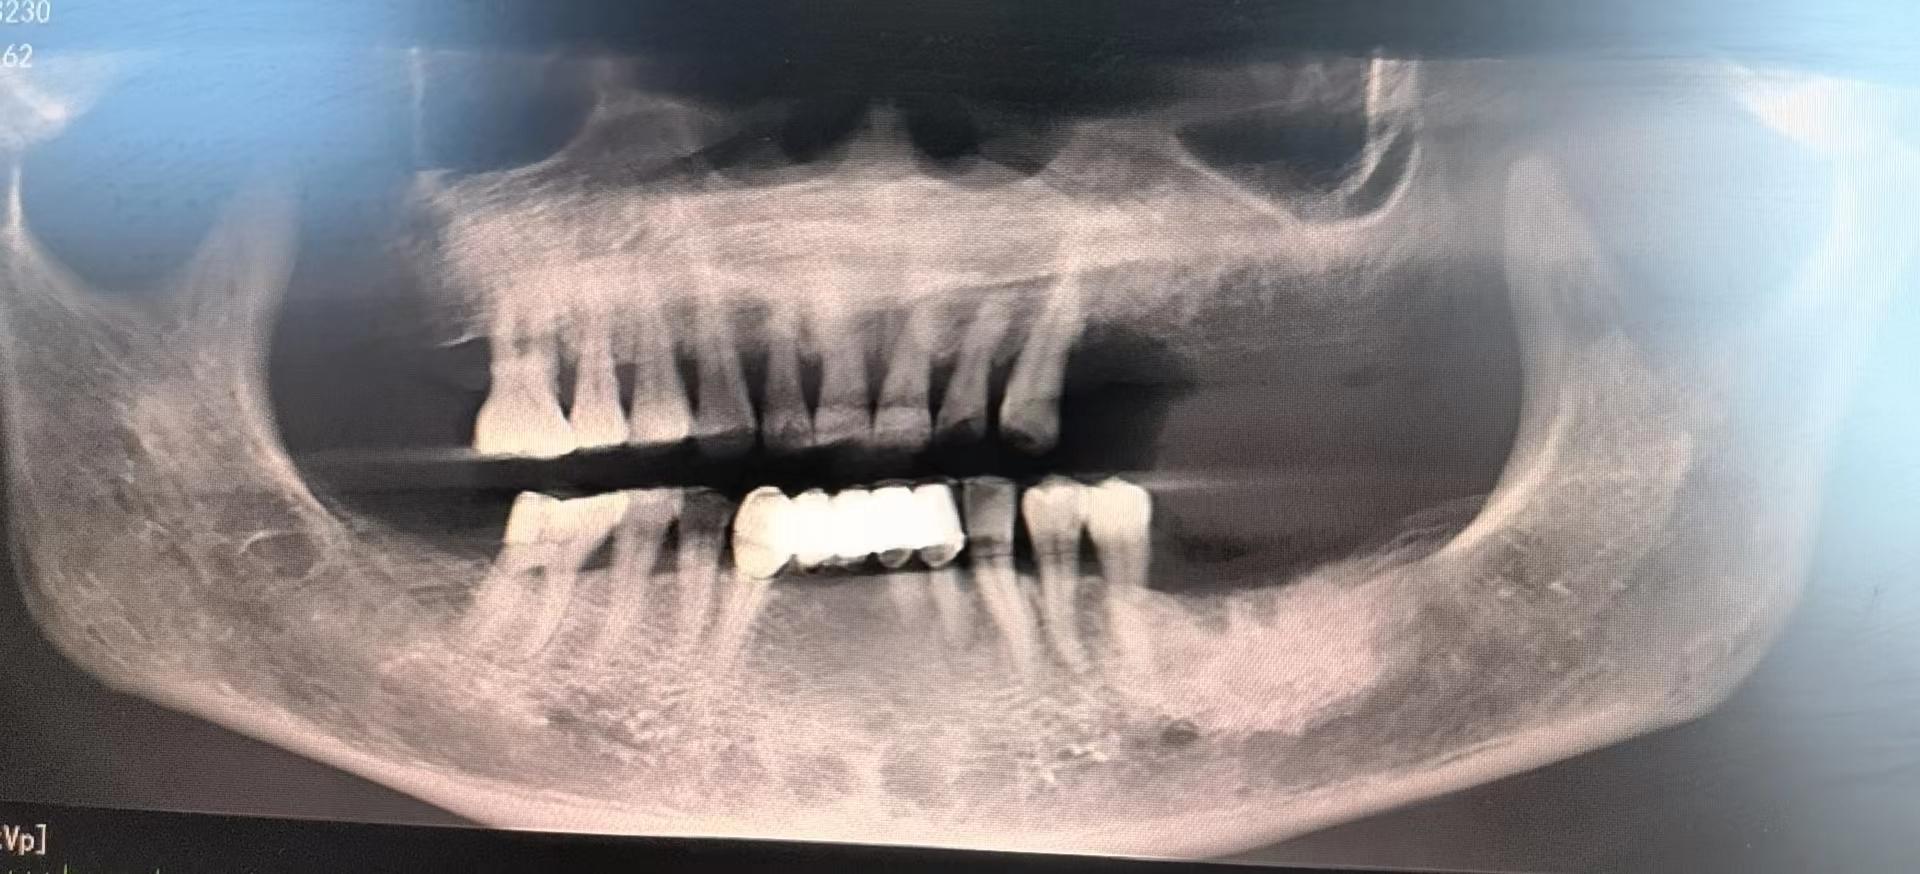

醫(yī)生檢查后,安排患者拍攝口腔CBCT,確定牙槽骨情況,并制定種植計(jì)劃,查血常規(guī),凝血功能,血壓,免疫檢查等。

為了避免患者在炎熱的夏季來(lái)回奔波,口腔科高艾玲主任團(tuán)隊(duì)決定為病人一次性種植三顆缺失的牙齒。辛璐醫(yī)生告訴患者,將通過(guò)牙科手術(shù)將人工牙根植入牙槽骨內(nèi),然后將牙齦縫合,大約10天左右拆線,之后等待骨愈合后進(jìn)行二期手術(shù)。